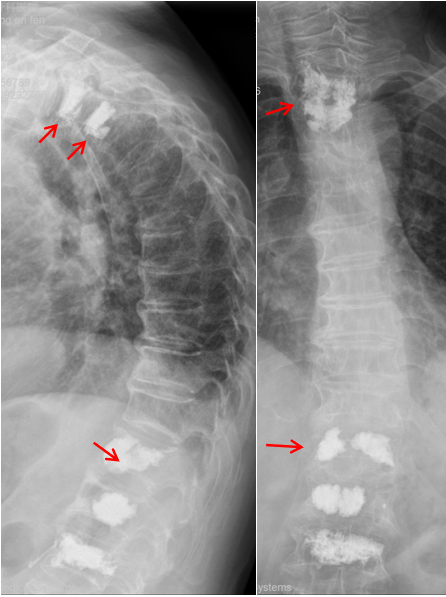

王阿姨的病情,从一开始就牵动着所有人的心。摔倒后,她随即出现胸部、肩背及腰部的剧烈疼痛,哪怕轻微咳嗽、翻身,疼痛都会急剧加剧,甚至连正常呼吸都变得困难。家人紧急将她送往北京积水潭医院贵州医院,经胸腰椎X线与核磁共振检查后,确诊其为胸2、胸3及胸12多发胸腰椎椎体压缩性骨折(图1),其中胸2、3、12椎体骨髓水肿明显,为导致她此次疼痛的“罪魁祸首”。

在C型X线及Dyla CT的实时精准引导下,穿刺针精准抵达胸2、3 椎体。团队随即通过穿刺针缓慢注入骨水泥,在C型X线实时监测下,骨水泥均匀填充至病变椎体中。整个手术历时40分钟,术中出血量不足5ml,术后即刻 X线显示:骨水泥分布均匀,无渗漏,周围脏器与神经未受任何损伤 —— 这场椎体成形术“相对禁区” 的攻坚战,以完美结果宣告成功。